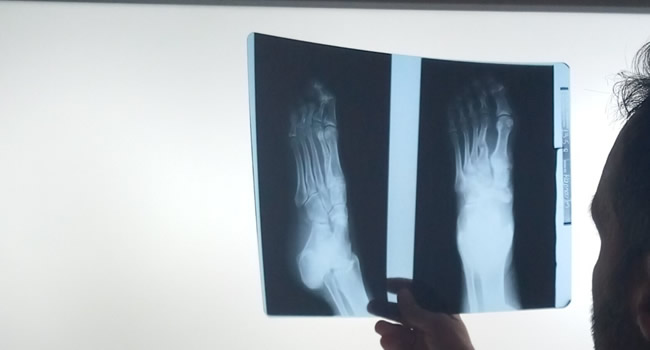

Οι ακτινογραφίες πραγματοποιούνται με πλήρως ψηφιακό εξοπλισμό και όχι ψηφιοποιημενο από έμπειρους Τεχνολόγους – Ακτινολόγους με άδεια ασκήσεως Επαγγέλματος.

Ο πιο σύγχρονος φορητός Ακτινολογικός εξοπλισμός πλήρως ψηφιακής απεικόνισης (DR) σε μια κινητή ακτινολογική μονάδα, μπορεί να επισκεφθεί τον ασθενή οπουδήποτε στην περιοχή της Θεσσαλονίκης και των περιχώρων και να σταλεί, αν ο ασθενής το επιθυμεί, η γνωματευμένη ακτινογραφία ηλεκτρονικά μέσω διαδικτύου στον θεράποντα- παραπέμποντα ιατρό ο οποίος θα λάβει το αποτέλεσμα στο προσωπικό του υπολογιστή, tablet, Smartphone οπουδήποτε κι αν βρίσκεται.

Άμεση παράδοση της ακτινογραφίας και της γνωμάτευσης λίγα λεπτά μετά την άφιξη της ακτινολογικής μονάδας. Δυνατότητα επανάληψης της ακτινογραφίας για την παραγωγή του βέλτιστου αποτελέσματος, εξαιτίας της ψηφιακής αυτόματης εμφάνισης της ακτινογραφίας που γίνεται στην οικία του ασθενούς